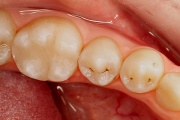

Ravijärgne seis. Jäävhammas on täielikult lõikunud.

) Röntgenülesvõte. Ülemise esimese jäävmolaari lõikumine on takistatud 2. piimamolaari tõttu

Esimese jäävmolaari ektoopiline lõikumine